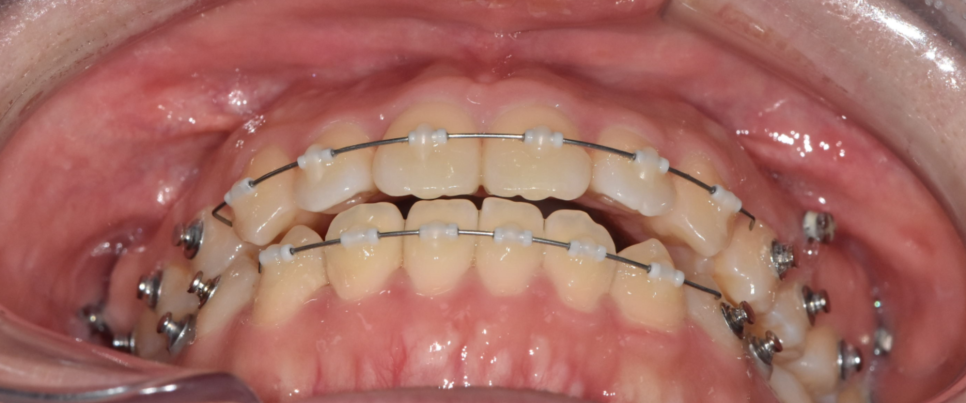

250622

기존 장치보다 세밀한 조정이 가능해서

짧은 시간 안에 원하는 위치로 치아를 유도할 수 있습니다.

미니스크류나 고무줄 사용이 병행될 수 있습니다.

치아 상태에 따라 다르지만,

앞니 부분 교정의 경우 평균 3~8개월 정도면

눈에 띄는 변화를 기대할 수 있습니다.